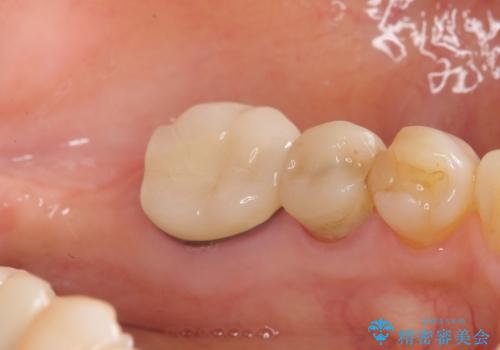

親知らずの移植 4年半経過症例 70代女性

- 親知らずの移植治療から4年半経過した患者様です。

他の歯の治療をご希望され、数年ぶりに来院して下さいました。

移植した親知らずは全く問題ないそうで、「まるで自分の歯のようです。本当にすごい技術ですね。」とおっしゃって下さいました。

歯肉の腫脹や退縮、動揺も認められませんでした。